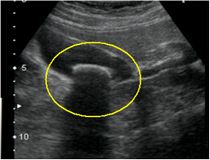

超音波画像

胆石症の診断には血液検査、超音波検査、CT検査が有用です。